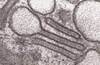

Birbeck granules under electron microscopy is diagnostic for which giant cell lesion?

Langerhans Cell Histiocytosis Also stains positive with CD1a and S100 (image)